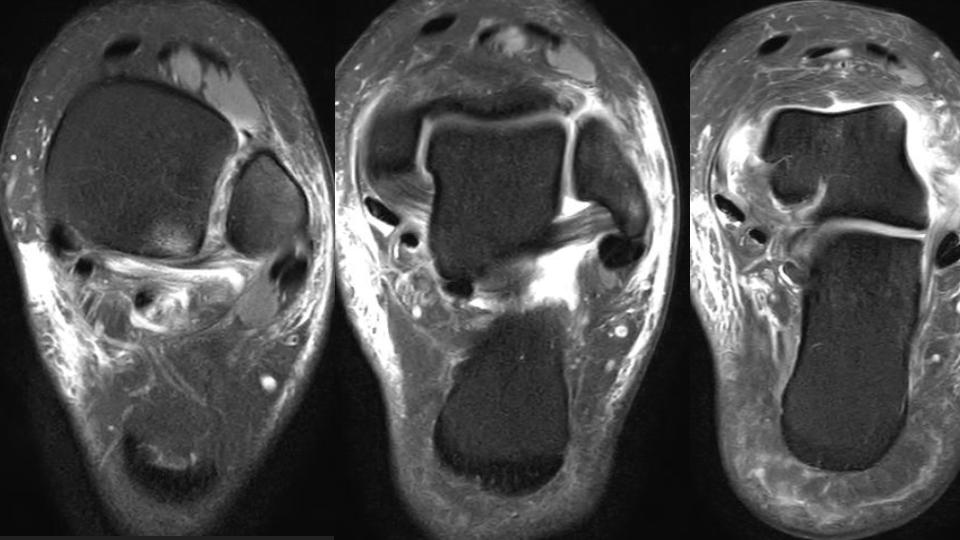

There is non displaced distal fibular shaft fx (see XR). There is a partial tear of the interosseous membrane (red arrows). There is complete AITFL rupture (white arrows). Gr I sprain of the PITFL and Laciniate ligaments. I think there is double band morphology of the ATFL, with a complete tear of one band and the other band intact (blue arrow). There is partial tear of the CFL (yellow arrow)...generally the CFL tears after the ATFL. The key point is that there should ALWAYS be overlap of the distal tibial and fibula in the Oblique or Mortise view...in this Obl view there is none. Syndesmotic Complex injury should have been suspected on the basis of the XR findings.

syndesmosis ( RID6088 )